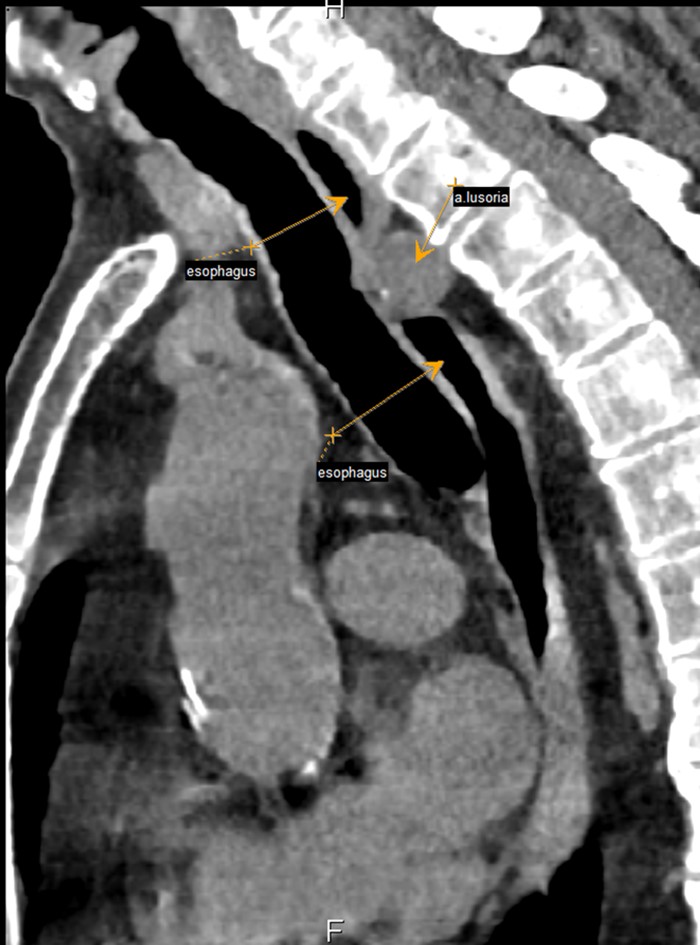

Рисунок 3 - Пациент А. 1955 г.р., сагиттальная проекция КТ органов грудной клетки

Примечание: стрелками указаны a. lusoria, расположенная между пищеводом и позвоночным столбом